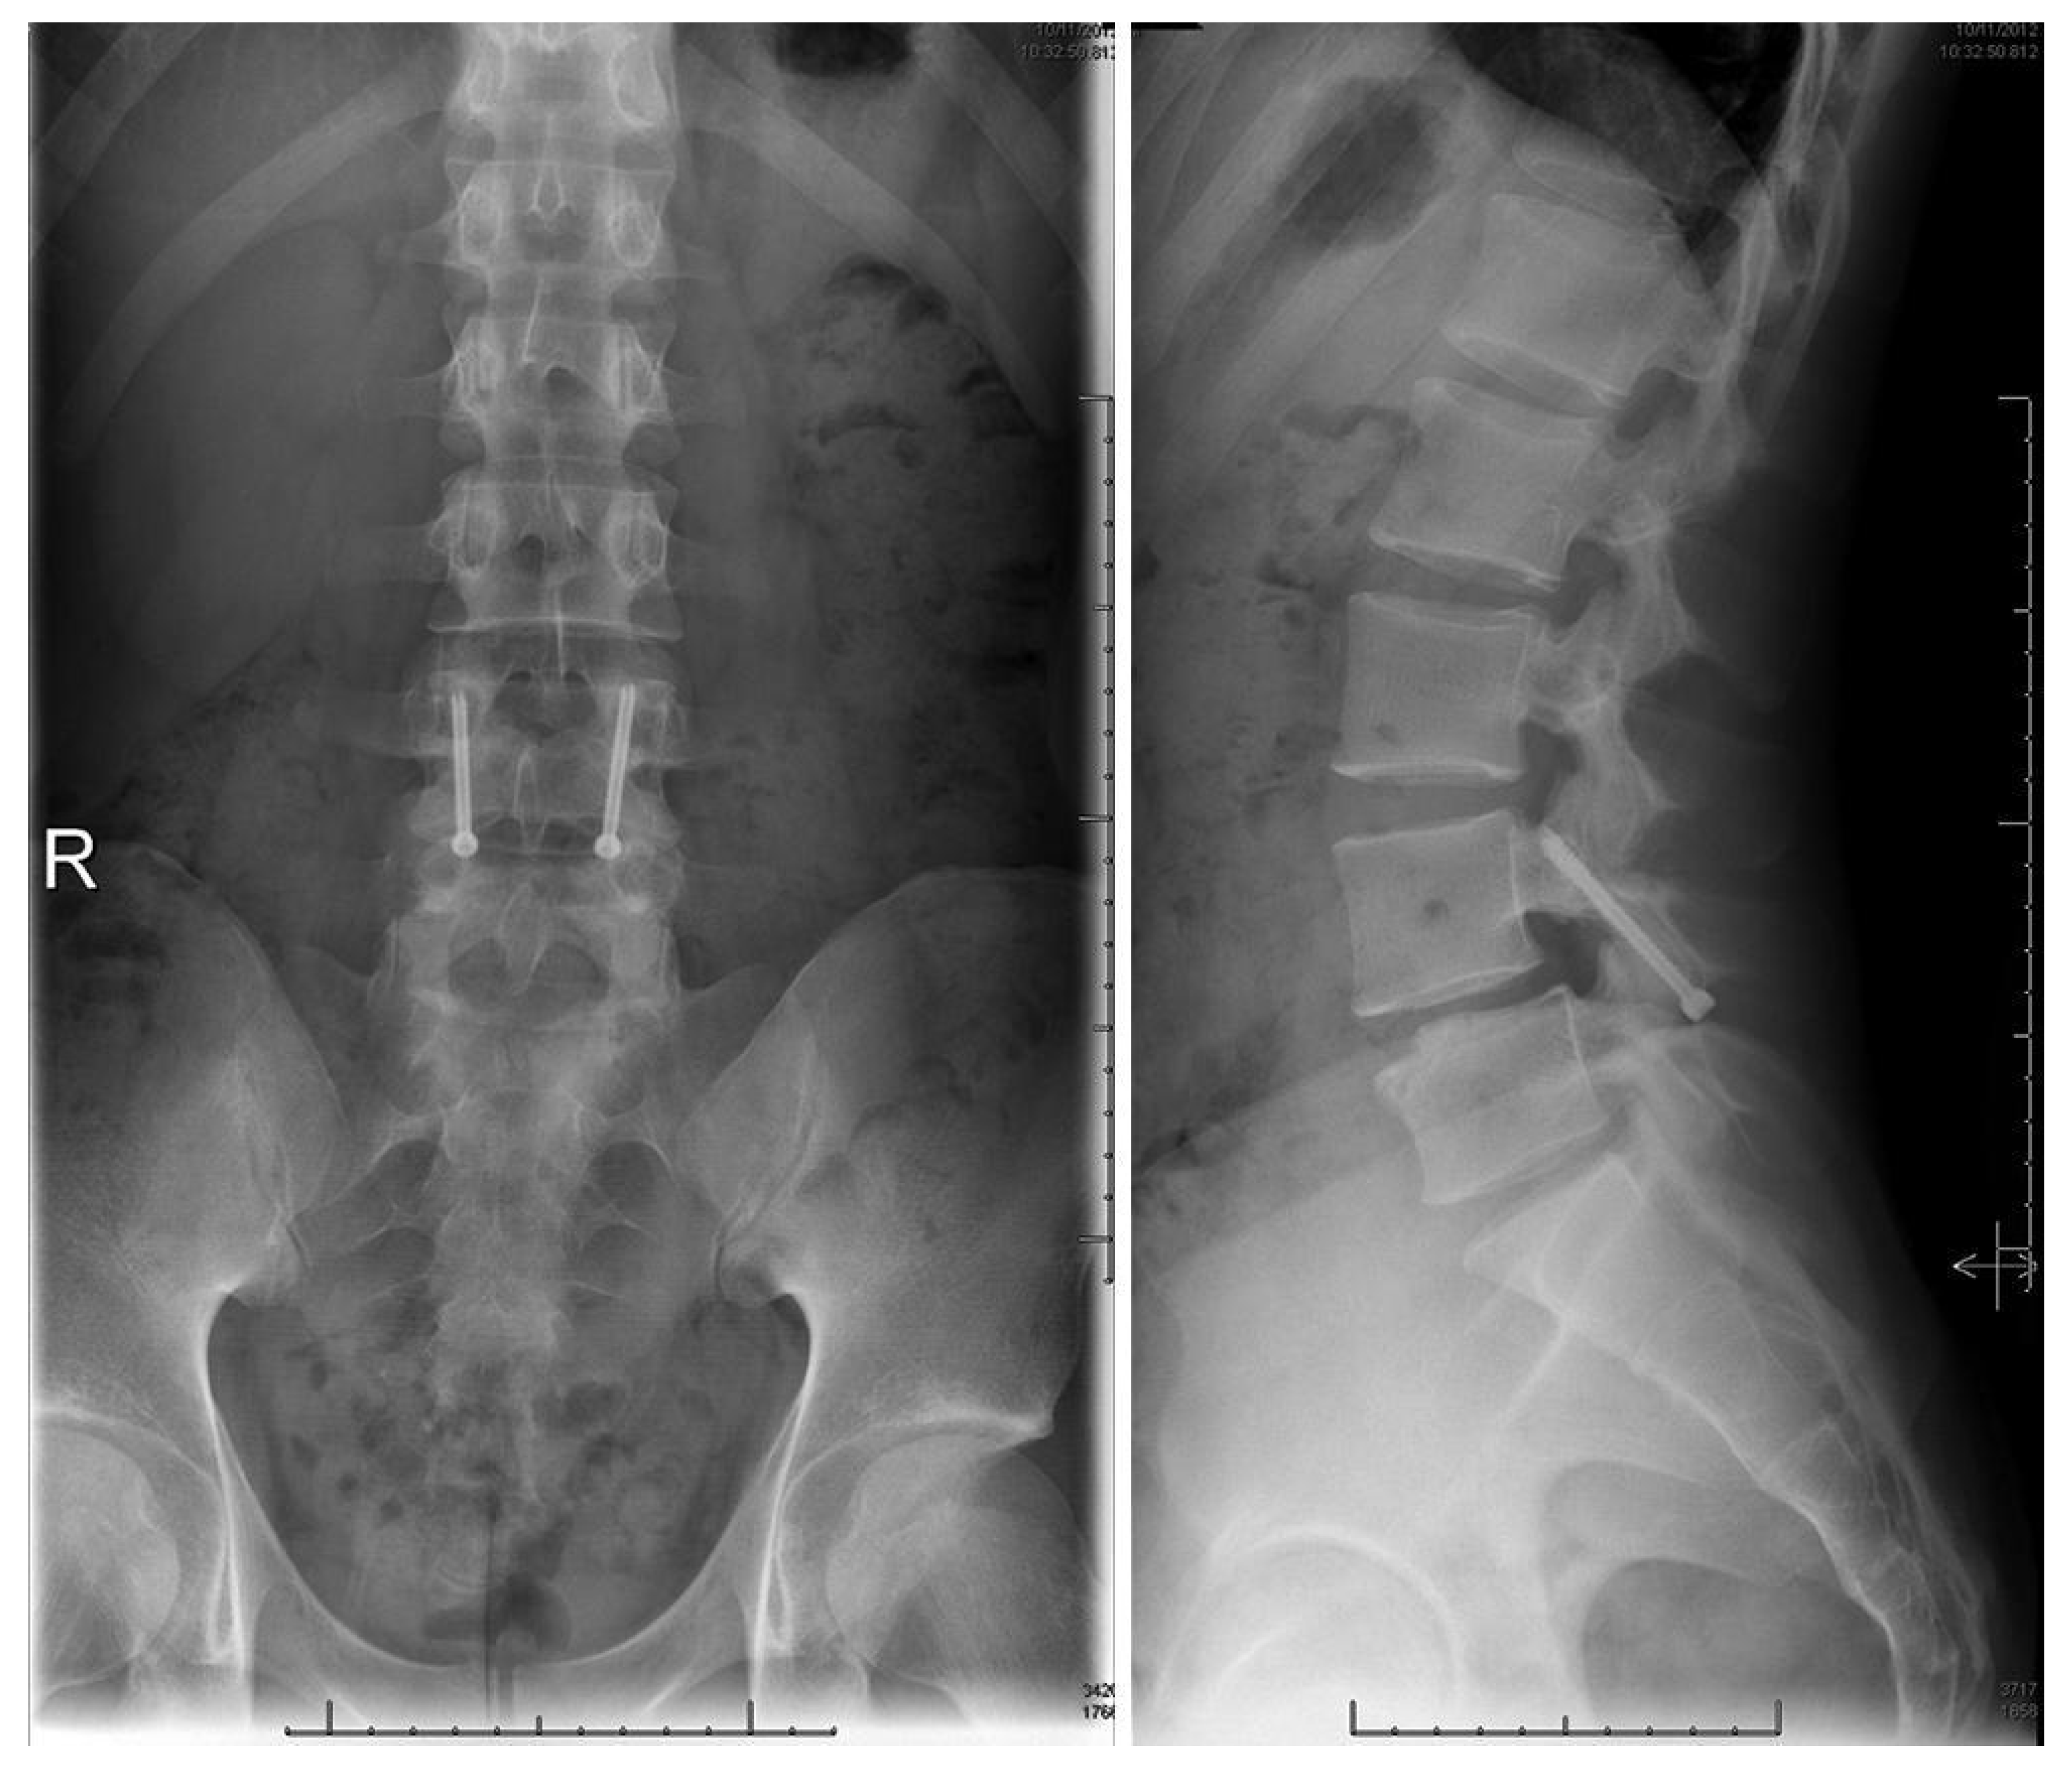

1.9.4. Pedicle Screw Based Repairs

Levi Technique—Minimally Invasive Direct Pars Screw Placement